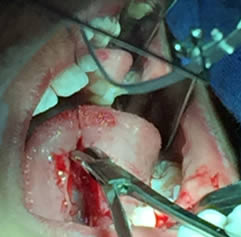

• Se realizó una incisión horizontal en la parte media del frenillo con hoja de bisturí No. 15 y mango No. 3, posteriormente se comenzó a cortar el frenillo de arriba abajo cuidando la anatomía de la región y la zona de las carúnculas sublinguales de los conductos de Wharton y Rivini. (Figuras 5 y 6).

Figuras 5 y 6. Incisión y corte del frenillo.

• Se eliminó el frenillo en su totalidad  con la ayuda de tijeras iris recta y hoja de bisturí del No. 15 así como todo el tejido residual fibroso correspondiente al frenillo. Se realizó genioplastia con pinza de mosco y disección roma para liberar adecuadamente la inserción frénica hasta la cara lingual de los incisivos inferiores. (Figuras  7, 8 y 9)

Figuras 7 y 8. Eliminación total del frenillo y genioplastia